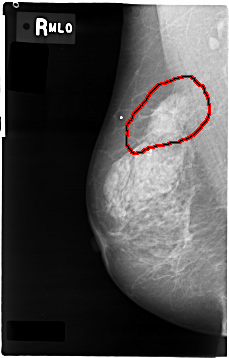

FILE: C_0004_1.RIGHT_MLO.OVERLAY

TOTAL_ABNORMALITIES 1

ABNORMALITY 1

LESION_TYPE MASS SHAPE IRREGULAR MARGINS SPICULATED

ASSESSMENT 5

SUBTLETY 5

PATHOLOGY MALIGNANT

TOTAL_OUTLINES 1

BOUNDARY